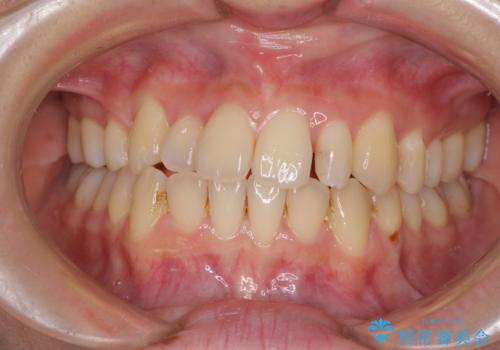

八重歯の抜歯矯正 補助装置を用いたインビザライン矯正

- 上顎の重なっている前歯を気にして来院された患者様です。

重なっている部分は抜歯が必要で、歯の移動量が多く、更には右側にずれている正中を改善する必要がありました。

インビザライン単体での治療は困難と判断し、補助装置により八重歯移動後にインビザラインを用いることとしました。

非常にしっかりとマウスピースを装着してくださいましたが、前歯の排列がなかなか仕上がらずに期間がかかってしまいました。